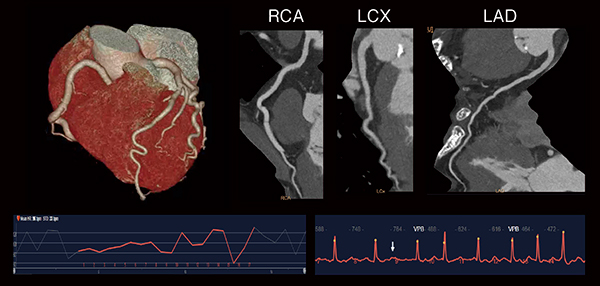

IQonにおける仮想単色X線(以下,MonoE)を用いた画像は,エネルギーを40keVから200keVまで連続的に可変して表示することができる。また,上記のanti-correlated noiseを除去することで,低いエネルギーのMonoE画像(以下,MonoE低keV画像)において,造影剤投与量を低減しても高画質で観察が可能となる。図3の腎機能低下症例では,造影剤を大幅に低減し,MonoE低keV画像を使用することで,低侵襲で診断能の高い検査が可能となっている。また,物質弁別を用いたヨード密度強調画像(以下,Iodine no water)では,ヨード造影剤のコントラストを強調することにより造影効果を有する箇所はさらに視認性が増し,従来のSECTでは診断困難なステント内再狭窄症例における低吸収プラークの視認性向上が期待できる(図4)。

図3 MonoE 50keVを用いた低造影剤量検査

造影剤使用量:9mL

(画像ご提供:みなみ野循環器病院様)